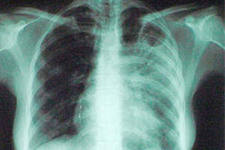

С целью своевременного выявления симптомов туберкулеза у населения кожно-венерологический диспансер г.Набережные Челны проводит открытый аукцион на оказание услуг по профилактическому приему врачом-фтизиатром на 2014 год. Необходимым условием заключения договора является наличие у специалиста лицензии по фтизиатрии, возможность комплексного клинико-рентгенологического, бактериологического и лабораторного обследования на туберкулез с использованием специализированных методик, Наличие компьютерной базы данных на больных туберкулезом.